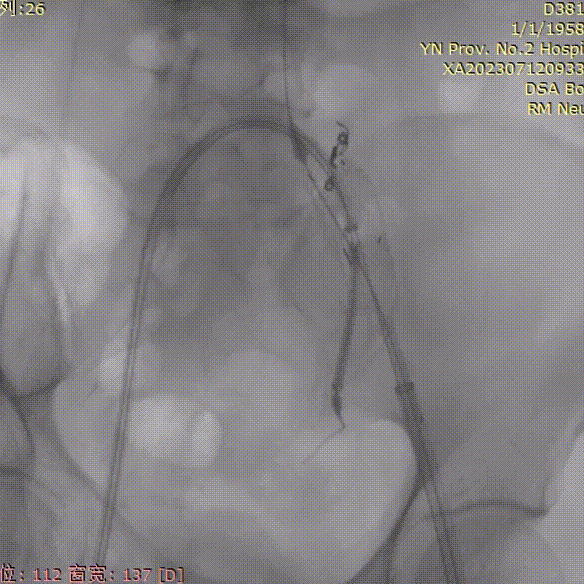

导管内手推造影,确认右髂内超选成功;

gore医疗怎么样「漫腹精论」双股动脉入路,纯腔内保双髂——GORE® EXCLUDER® 髂动脉分支型覆膜支架(IBE)治疗双侧髂总动脉_https://www.jmylbn.com_新闻资讯_第23张

右髂内支架通过IBE短腿后,整体往下拉IBE,将IBE短腿拉至右髂内动脉开口上方;

gore医疗怎么样「漫腹精论」双股动脉入路,纯腔内保双髂——GORE® EXCLUDER® 髂动脉分支型覆膜支架(IBE)治疗双侧髂总动脉_https://www.jmylbn.com_新闻资讯_第24张